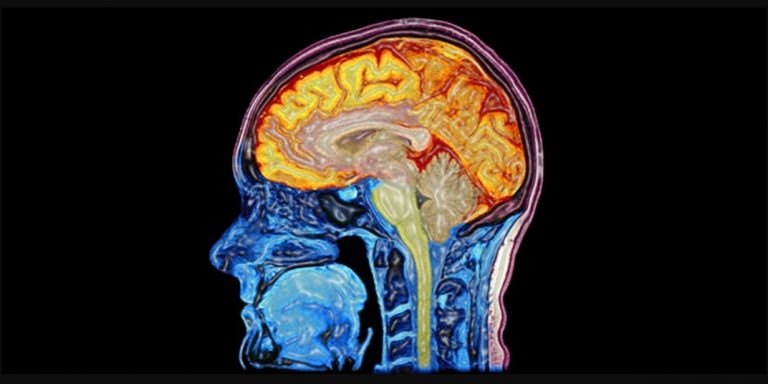

Unlike most cells in the body, when brain cells are damaged or destroyed they will not regrow. This means that when you suffer a brain injury, your brain has to try to reorganise itself to compensate, with different parts taking over the functions of the damaged cells. This is known as “brain plasticity”.

The process of your brain reorganising itself involves new nerve pathways being established through healthy cells, bypassing the damaged areas. This process is not always 100% effective, however. That is why there may be some permanent loss of function that translates to a degree of lasting physical and/or mental disability.